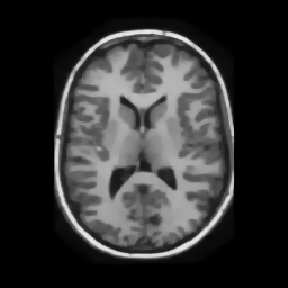

Reconstructing under-sampled k-space measurements in Compressed Sensing MRI (CS-MRI) is classically solved with regularized least-squares. Recently, deep learning has been used to amortize this optimization by training reconstruction networks on a dataset of under-sampled measurements. Here, a crucial design choice is the regularization function(s) and corresponding weight(s). In this paper, we explore a novel strategy of using a hypernetwork to generate the parameters of a separate reconstruction network as a function of the regularization weight(s), resulting in a regularization-agnostic reconstruction model. At test time, for a given under-sampled image, our model can rapidly compute reconstructions with different amounts of regularization. We analyze the variability of these reconstructions, especially in situations when the overall quality is similar. Finally, we propose and empirically demonstrate an efficient and data-driven way of maximizing reconstruction performance given limited hypernetwork capacity. Our code is publicly available at https://github.com/alanqrwang/RegAgnosticCSMRI.